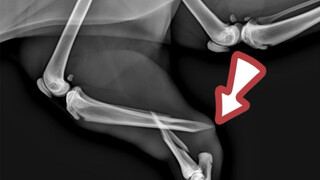

Ketika penyelamat melihatnya, kondisinya sudah seperti ini, ini bisa dibilang nasib buruk